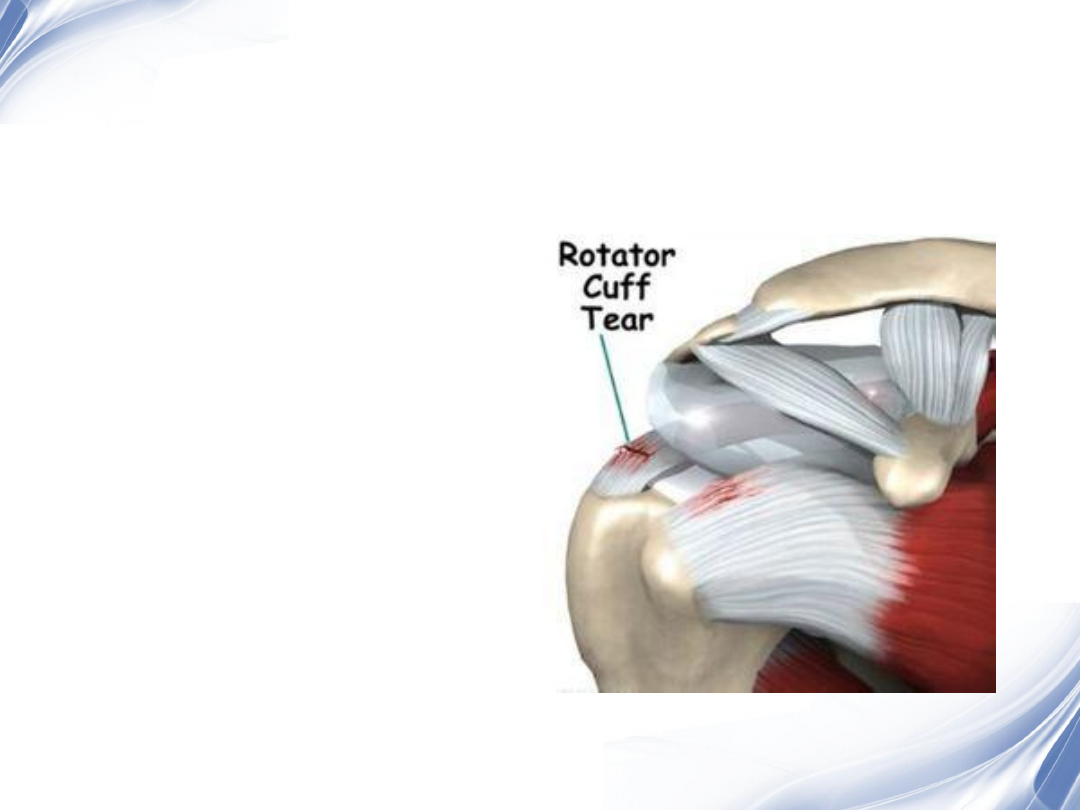

肩袖撕裂

将撕裂的肩袖拉回止点,

重新固定,恢复病人肩关

节的正常功能